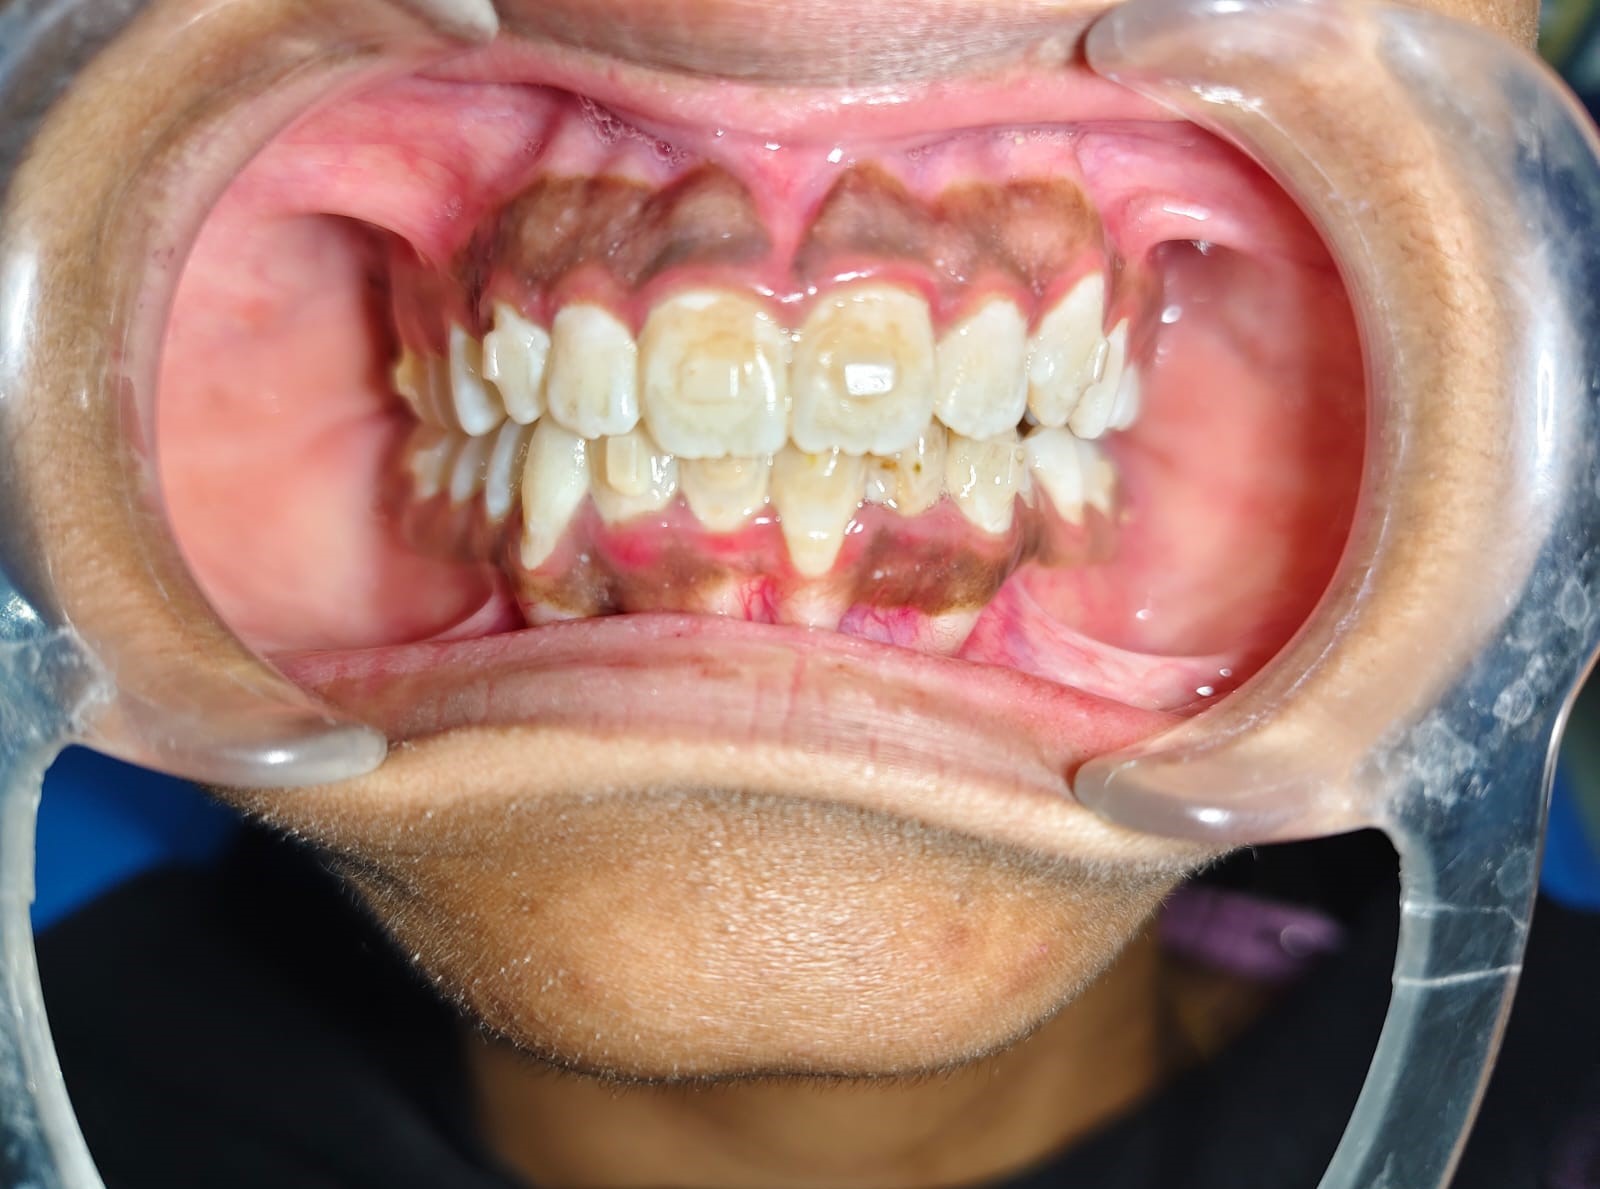

Sairam dental care located in Dharmapuri, with Leading Dentist In Oddapatti, is the Dental Hospital with exclusive root canal, Braces & Invisalign center. Led by renowned Drs Raghuraaman ( Periodontist) and Nivetha Raghuraaman ( Orthodontist) Sairam dental care offers gum treatment with expertise in laser, root canal treatment and digital smile correction with advanced technology aim to focus on aesthetics, comfort and precision. The clinic also specializes in Invisalign treatment, digital smile makeover, laser gum care, dental implants, root canal therapy, extractions and full-mouth rehabilitation blending compassionate care and clinical excellence.